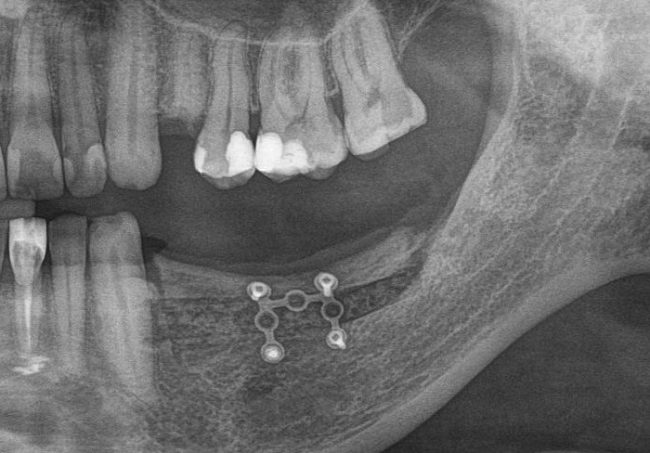

После операции мы делаем контрольные снимки. Это может быть ортопантомография:

или конусно-лучевая компьютерная томография. Как вам больше нравится.

Результат остеопластики методом остетотомии мы можем оценить уже через 4 месяца. Перед этим сделаем контрольные снимки (слева «до», справа «через 4 мес»):